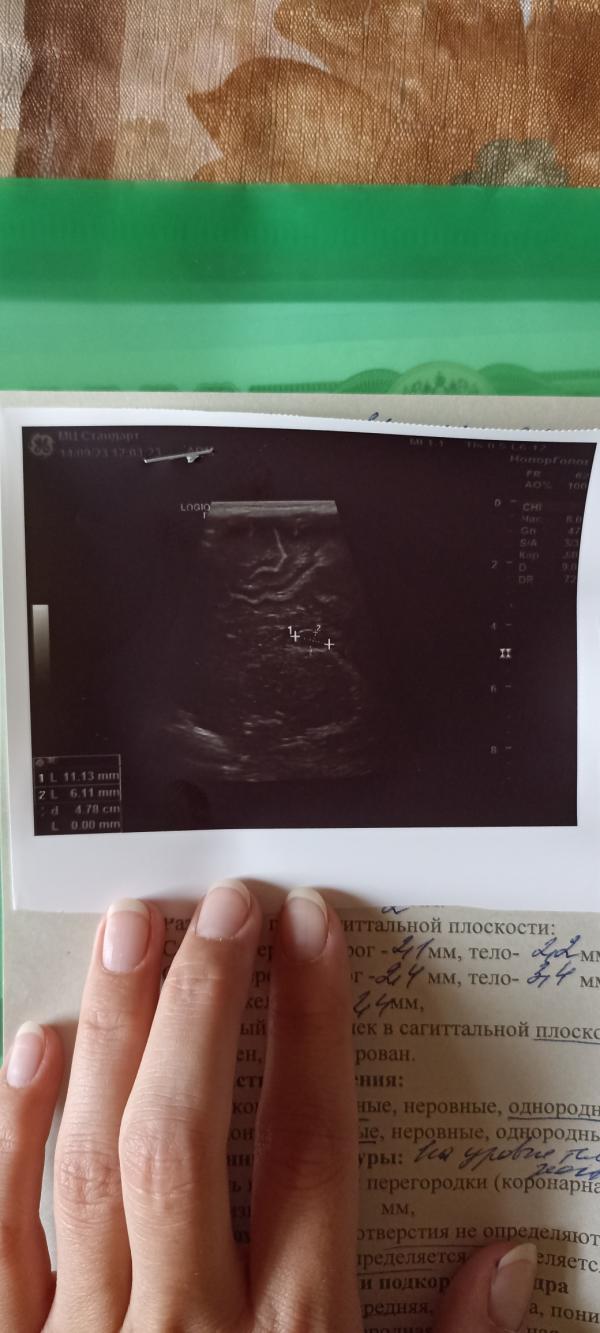

В месяц нашли кисту. У невролога были в марте (в 5 мес), сказала мол ничего страшного. В прошлый раз узи делали в 6 месяцев и вот только что с УЗИ. Киста увеличилась... Нервничаю до ужаса. К врачу через 2 недели и к неврологу тоже.

Насколько увеличилась? И кстати не факт, что увеличилась, тк узи далеко не самый точный метод визуализации, очень зависим от специалиста и аппарата

@nata_lee_ я уже тоже об этом думала. Она сначала наметилась вообще 14х9, потом перемеряла много раз

И может кто заключение от руки расшифровать может? Нифига не понятно написала